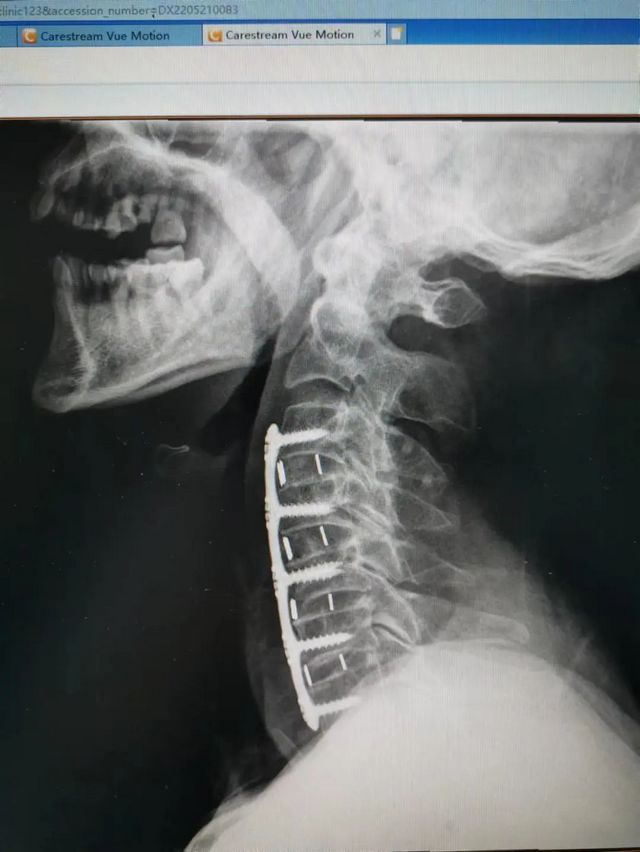

杨先生术后拍片

由于杨先生的病情严重,需住院治疗。杨先生入院后,泸州市中医医院骨伤二科科主任杨陈一制定了手术计划,决定脊髓型颈椎病的手术从前路切开减压,颈3/4 、颈4/5、 颈5/6、 颈6/7椎间盘切除,椎间融合,钢板内固定术手术,而腰椎管狭窄症经后路切开减压,腰3/4、腰4/5椎同盘动除,椎间融合、钉棒系统内固定术。